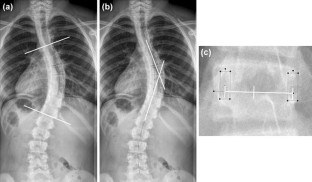

Fig. 1